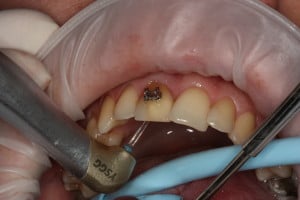

Przykład ekstruzji ortodontycznej za pomocą płytki termoformowalnej i zameczka ortodontycznego: